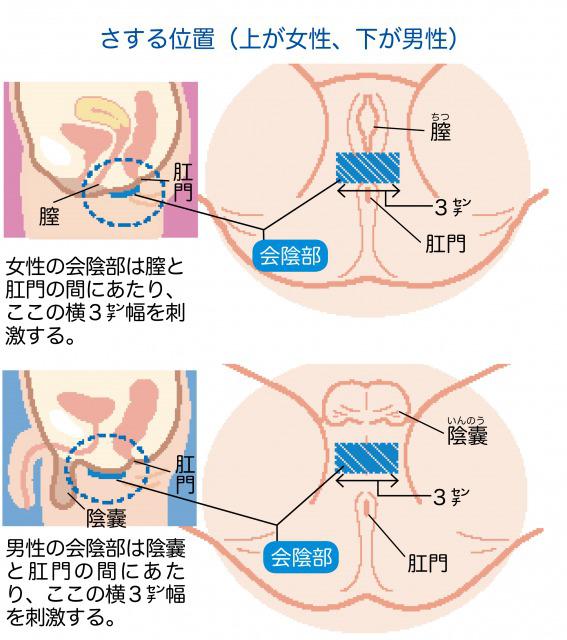

男の尿トラブルの主犯は前立腺肥大 ちょい漏れは会陰部指圧で解決 尿のトラブル 自力で解決 日経gooday グッデイ

夜間頻尿を招く 過活動膀胱 の改善運動 骨盤底さすり のやり方 公的機関の研究者が解説 カラダネ